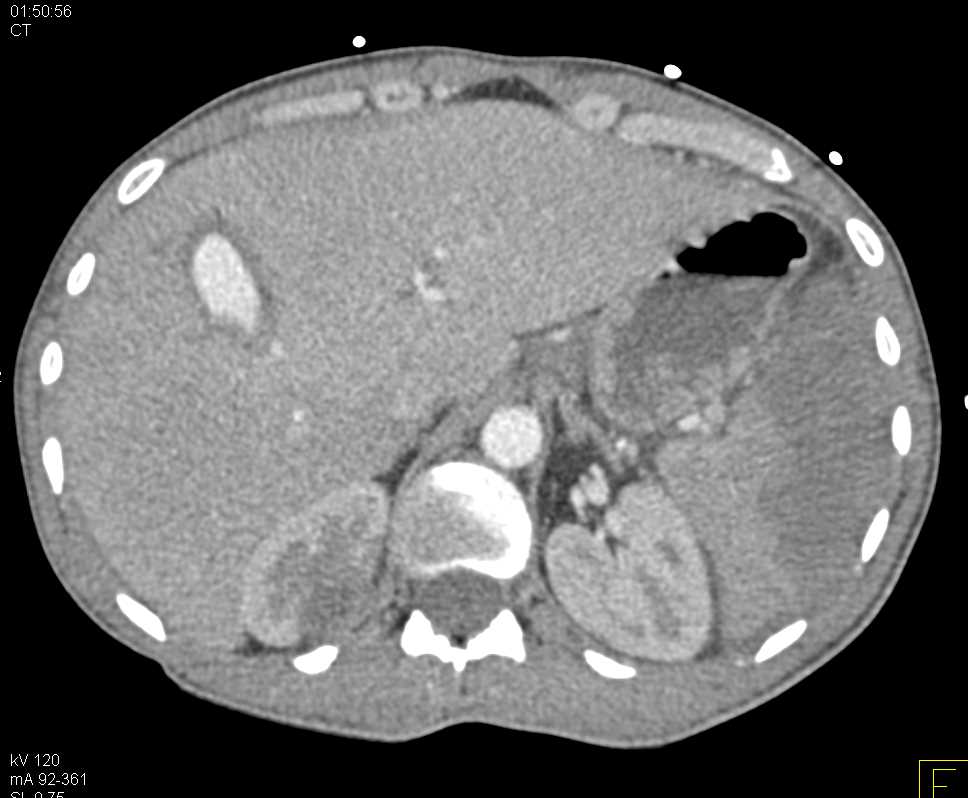

Multiple Hepatic Lacerations Following Trauma